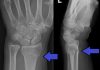

Şekil 1: Volar Tip Barton kırığı

Dorsal Barton Kırığı: Radius alt uç eklem yüzünün oblik dorsal kenar kırığıdır. Aynı zamanda dorsale doğru radyokarpal çıkık vardır. Radiokarpal eklem dislokasyonu Barton kırıklarının karakteristik özelliğidir. Radius distal artiküler yüzünün kopma tipi kırıklarıdır. El bileğinin etkilenme anında dorsifleksiyonda olduğu radiokarpal eklem yüzeyinin yüksek hızda darbe aldığı durumlarda oluşur.

Volar Barton Kırığı: Daha yaygıdır. Radius alt uç eklem yüzünün volar kenar kırığıdır. Volare doğru radyokarpal çıkıkta mevcuttur. Dorsal Barton kırığıyla aynı mekanizmayla oluşur ama el bileği yaralanma anında volar fleksiyondadır. Ters Barton kırığı da denir. Radius volar yüzünden kama şeklinde artiküler parçanın koptuğu görülür ve kırıkla beraber el bileği ekleminin volar çyönde çıkar.